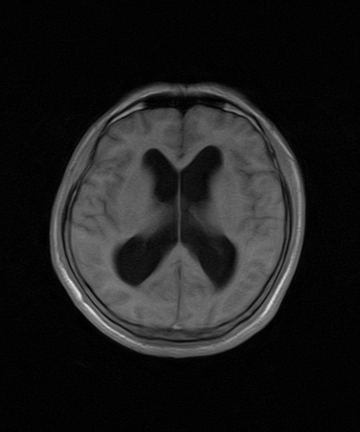

标题: MRI2064:少见病例。男性52,视力下降多年。 [打印本页]

标题: MRI2064:少见病例。男性52,视力下降多年。

四脑室区见混杂信号占位影,脑室系统扩张明显,临近结构显著受压称位,患者52岁,多考虑室管膜瘤可能性大

考虑第四脑室室管膜瘤并阻塞性脑积水。

考虑第四脑室室管膜瘤并梗阻性脑积水;部分性空蝶鞍;左侧上颌窦粘膜下囊肿。

考虑第四脑室室管膜瘤【血供丰富血管母细胞瘤可能】并梗阻性脑积水;部分性空蝶鞍;左侧上颌窦粘膜下囊肿。